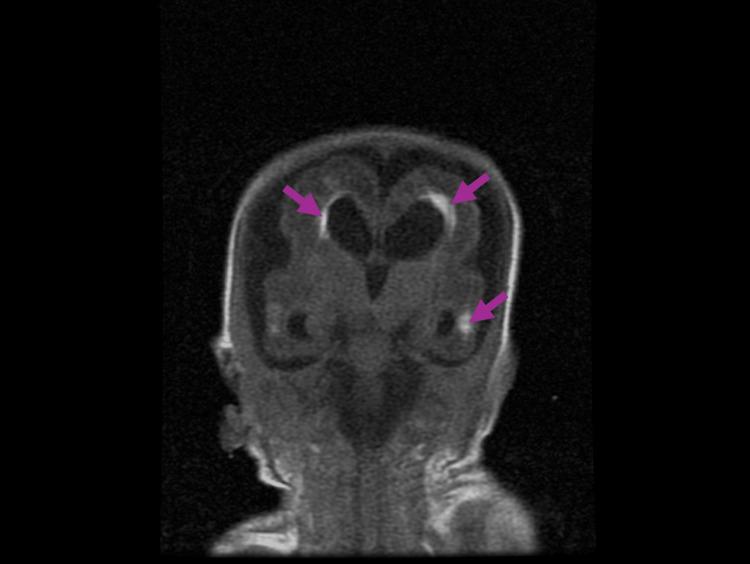

This case report investigates the management of a 24-week-old neonate with congenital cytomegalovirus (CMV) infection and its sequelae, including severe intrauterine growth restriction, thrombocytopenia, and brain anomalies, ultimately progressing to lissencephaly. The diagnostic challenges included delayed clinical suspicion of congenital CMV, which was not identified until after delivery through CMV DNA polymerase chain reaction, and differentiating its symptoms from other potential causes of the neonate's condition. Aggressive interventions included antibiotics, antiviral therapy with ganciclovir, and supportive measures such as intubation, CPR, respiratory support, blood transfusions, and management of coagulopathy. Despite these efforts, the patient deteriorated due to progressive hypoperfusion, hypoxemic cardiorespiratory failure, and disseminated intravascular coagulopathy. Due to the poor prognosis and extent of multiorgan damage, support was withdrawn per parental consent. This case highlights the complications encountered when managing an advanced-stage neonatal CMV infection and emphasizes the importance of a multidisciplinary and holistic approach to guide diagnosis and treatment.

本病例报告探讨了一名24周大先天性巨细胞病毒(CMV)感染新生儿及其后遗症的治疗情况,这些后遗症包括严重的宫内生长受限、血小板减少症和脑异常,最终发展为无脑回畸形。诊断面临的挑战包括先天性CMV的临床怀疑延迟,直到分娩后通过CMV DNA聚合酶链反应才得以确诊,以及将其症状与新生儿病情的其他潜在病因相区分。积极的干预措施包括使用抗生素、更昔洛韦抗病毒治疗,以及诸如插管、心肺复苏、呼吸支持、输血和凝血病管理等支持措施。尽管采取了这些措施,患者仍因进行性低灌注、低氧性心肺衰竭和弥散性血管内凝血而病情恶化。由于预后不良和多器官损伤程度严重,经家长同意停止了支持治疗。本病例突出了晚期新生儿CMV感染治疗中遇到的并发症,并强调了多学科整体方法在指导诊断和治疗方面的重要性。